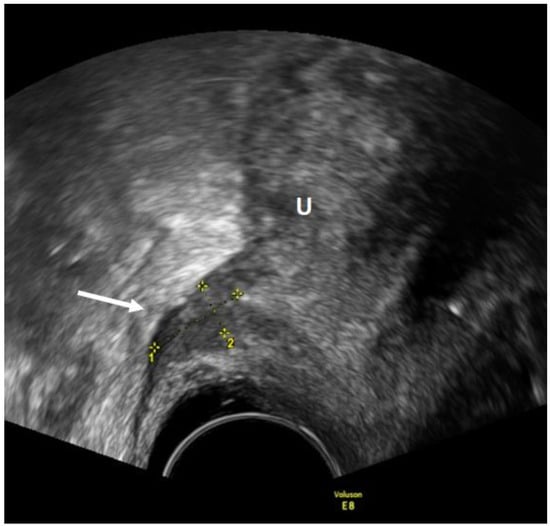

- Leonardi, M.; Martins, W.P.; Espada, M.; Arianayagam, M.; Condous, G. Proposed technique to visualize and classify uterosacral ligament deep endometriosis with and without infiltration into parametrium or torus uterinus. Ultrasound Obstet. Gynecol. 2019, 55, 137–139. [Google Scholar] [CrossRef]